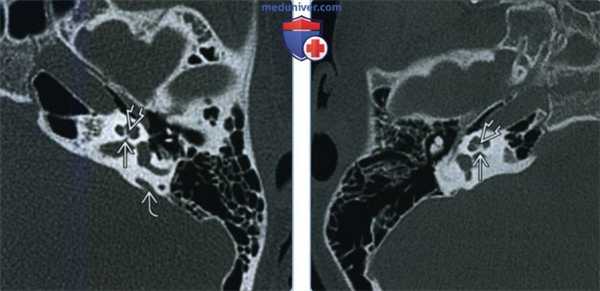

(Слева) При аксиальной КТ в костном окне у девочки 11 лет с глубокой двухсторонней нейросенсорной тугоухостью (НСТУ) определяется тяжелый стеноз канала улиткового нерва (КУН). Стержень и камеры улитки выглядят асимметричными. Определяется также легкое расширение водопровода преддверия.

(Справа) При аксиальной КТ в костном окне у четырехлетней девочки с глубокой правосторонней НСТУ определяется отсутствие КУН и выраженное утолщение стержня.

3. КТ при аплазии-гипоплазии улиткового нерва и канала улиткового нерва:

• КТ в костном окне:

о КУН:

- Норма: в некоторых случаях НУН на МРТ

- Стеноз: тяжесть варьирует

- Атрезия: полное отсутствие КУН

о Улитка:

- Нормальные завитки и нормальный стержень, нормальный или незначительно стенозированный КУН

- Нормальные завитки, утолщенный стержень, умеренный или тяжелый стеноз КУН

- Аномалия улитки со стенозом/атрезией КУН (менее типична), например, гипоплазия улитки

о Преддверие и полукружный канал (ПКК): норма (чаще всего); реже аномалии (синдромной этиологии)

о ВСК: норма или уменьшение, редко-отдельный канал ЧН VII («удвоение ВСК»)

о Канал ЧН VII: норма (чаще всего) или аномалия (редко)

(Слева) При аксиальной МРТ Т2 SPACE у годовалого мальчика с глубокой левосторонней НСТУ визуализируется нормальный УН справа, преддверные нервы с обеих сторон не изменены. Левый УН отсутствует, КУН слева слегка стенозирован.

(Справа) При сагиттальной косой MPT Т2 SPACE у годовалого мальчика с глубокой левосторонней НСТУ левый УН отсутствует, видны нормальные преддверные нервы и лицевой нерв.